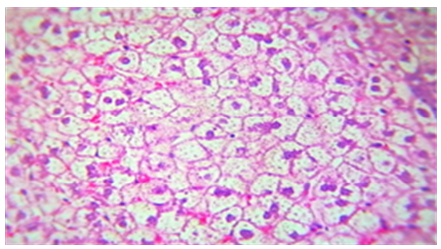

Figure 6. The histological slice of the liver treated with Nystatin and C. Krusei revealed: steatosis is present in wide areas of liver

Figure 7. Histological slice of the C. krusei-treated liver revealed: steatosis is present in wide areas of liver

Figure 8. Histological slice of the C. krusei-treated liver revealed: S) steatosis are present with patch of hepatocytes. LI) Lymphocytes infiltration